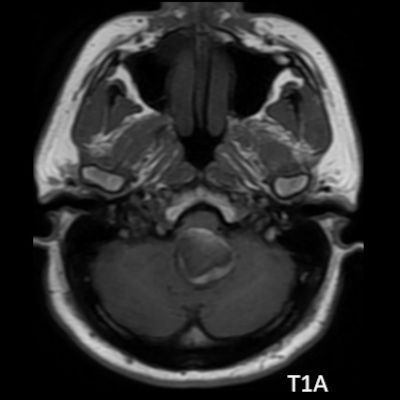

- A. Posterior fossada, T2A, T1A görüntü ve SWAN sekanslarda, 3.5 cm boyutta, düzgün sınırlı, T1A hiperintens, T2A hipointens heterojen iç yapıda kitlesel lezyon izleniyor (çember). Lezyonun serebellum ve kraniyoservikal bileşkeye bası etkisi mevcuttur (ok). Lezyon periferinde T1A, T2A ve SWAN görüntülerde hiperintens tubuler yapı bulunmaktadır (ok). Bu yapı intralezyonel “yılanvari eksantrik vasküler’’ yapıdır.

- Kısmen tromboze olmuş dev serebral anevrizma, kan ürünlerinin değişken yaşına bağlı olarak MRG’de heterojen bir sinyale sahiptir.

- T1 kısmen tromboze anevrizmada genellikle hiperintens odaklarla heterojen